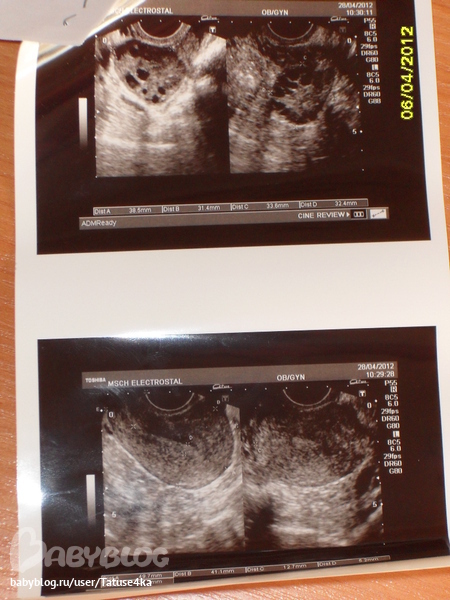

ФолликулометрияУ меня сегодня 40ДЦ,обычный цикл 30дней,задержка значительная,сходила на УЗИ,ну размеры матки и Я писать не буду,но смутило меня вот что:эндометрий 5.6мм и фолликулы 5-6мм,что соответствует 1 фазе.

В связи с этим вопросы,как может быть соответствие 1 фазе если М нет и не было?Может ли быть что О пришла по планы а М так и наступили?Может ли это быть Б? и почему эндик и фол-лы такие маленькие,с чем это может быть связанно?

Я когда пришла с УЗИ посмотрела все мои узи за последние пол года и увидела что если у меня и была задержка,то хотя бы эндометрий был ок.13-16мм,а сейчас вот что.К врачу пойду 2 или 3 числа,а сейчас помогите разобраться,перерыла весь инет так ничего путного не нашла.Переживаю очень.

Что касается вашего пролактина. Как врач интересно может сказать, что его надо сдавать на 3-8 день цикла, если пролактин фазы не имеет? Почитайте в интернете.Плюс в правом яичнике фолликулов нет что ль? Я вам прямо скажу, если ваш мочевой пузырь был пуст и вы делали обычное УЗИ (не трансвагинальное), то увидеть фолликулы 5-6 мм будет почти невозможно. Плюс еще поставили поликистоз яичников, на каком основании, блин?

спасибо,я делала трансвагинальное узи но на пустой мочевой пузырь.Может и вправду завтра сходить к другому врачу на УЗИ.

хм..трансвагинальное-другое дело. Там не нежуен полный мочевой пузырь. Но все равно, что-то странно....

НУ к примеру. правый Я. чуть больше, но там даже про фолликулы ничего не написали. Какое-то скупое заключение. Но решать вам. удачки..